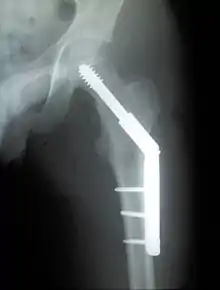

Trochanteric fracture

Fracture supported by dynamic hip screw

A trochanteric fracture, below the neck of the femur, has a good chance of healing.

Closed reduction may not be satisfactory and open reduction then becomes necessary.[42] The use of open reduction has been reported as 8-13% among pertrochanteric fractures, and 52% among intertrochanteric fractures.[43] Both intertrochanteric and pertrochanteric fractures may be treated by a dynamic hip screw and plate, or an intramedullary rod.[42]

The fracture typically takes 3–6 months to heal. As it is only common in elderly, removal of the dynamic hip screw is usually not recommended to avoid unnecessary risk of second operation and the increased risk of re-fracture after implant removal. The most common cause for hip fractures in the elderly is osteoporosis; if this is the case, treatment of the osteoporosis can well reduce the risk of further fracture. Only young patients tend to consider having it removed; the implant may function as a stress riser, increasing the risk of a break if another accident occurs.